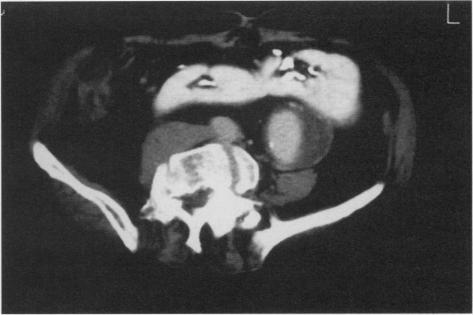

Horseshoe kidney is a rare congenital anomaly that can create various technical problems during surgery for repair of abdominal aortic aneurysm. The diagnosis of this anomaly should be confirmed preoperatively in order to plan surgical strategy. Nowadays, in more than 90% of all cases, ultrasonography, contrast computerized tomography, urography, and angiography are the best instrumental methods of detecting this anomaly in association with abdominal aortic aneurysm. The transperitoneal approach assures the best exposure of the kidney, the ureters, the aneurysm, and both iliac vessels, but the renal isthmus can pose a problem in reimplanting aberrant renal arteries. When it is known preoperatively that renal revascularization should be performed, the left extraperitoneal approach is a better choice. In any event, the coexistence of horseshoe kidney and abdominal aortic aneurysm does not preclude the treatment of the latter. In elective surgery of abdominal aortic aneurysm, the morbidity and mortality rates in the presence of horseshoe kidney are much the same as those in the presence of normal kidneys. The best results in this kind of surgery are obtained by adapting one's surgical technique to each anatomical variant that is encountered.

马蹄肾是一种罕见的先天性异常,在腹主动脉瘤修复手术过程中可能会引发各种技术问题。术前应确诊这种异常情况,以便制定手术策略。如今,在所有病例中,超过90%的情况下,超声检查、计算机断层扫描造影、尿路造影和血管造影是检测这种与腹主动脉瘤相关异常的最佳影像学方法。经腹途径能确保对肾脏、输尿管、动脉瘤以及双侧髂血管的最佳暴露,但肾峡部在重新植入异常肾动脉时可能会带来问题。如果术前已知需要进行肾血管重建,左腹膜外途径是更好的选择。无论如何,马蹄肾与腹主动脉瘤并存并不妨碍对后者的治疗。在腹主动脉瘤择期手术中,存在马蹄肾时的发病率和死亡率与存在正常肾脏时大致相同。这类手术的最佳效果是通过根据所遇到的每种解剖变异调整手术技术来实现的。